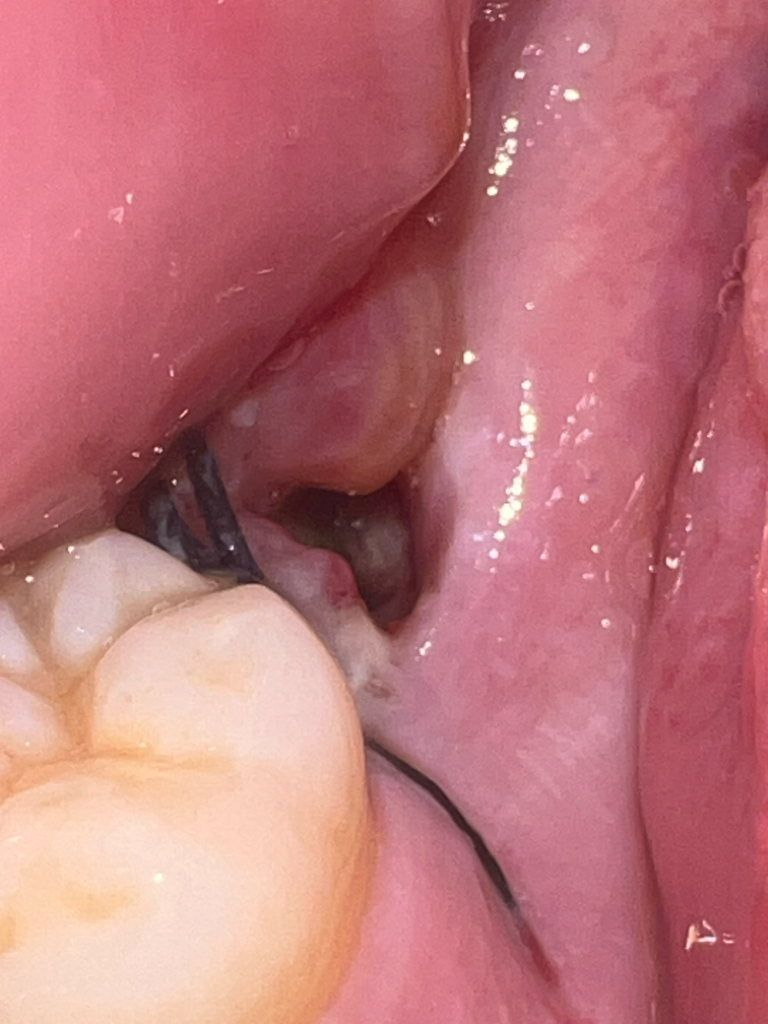

2월6일 사랑니 발치후에 통증이 계속되요 혹시 드라이 소켓인가요??

사랑니를 발치 하고 발치한 부위를 오늘 확인 하였더니 구멍에 흰색? 누런색 무언가가 보입니다 혹시 드라이 소캣일까요?

• 1번 째 사진

현재 드라이소켓은 아닌 혈병으로 보이며 아무는 과정의 자연스런 현상입니다. 발치후 주변잇몸에 통증이 나타나는 경우 있으며 통증이 심한 경우 소염진통제 복용을 권합니다.